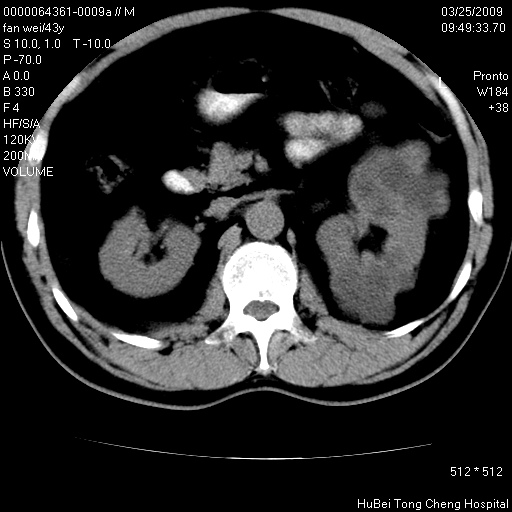

双肾ct轴位平扫+增强扫描(层厚10mm,螺距1.0,重建间隔10mm),图像如下:

双肾多发性囊肿

双侧多囊肾!

双肾多发性囊肿   脂肪肝

囊肿数得清,肾功能正常,考虑多发肾囊肿.另外,右肾后极突向肾周间隙的那个病灶是不是错构瘤,请楼主调窗看看.